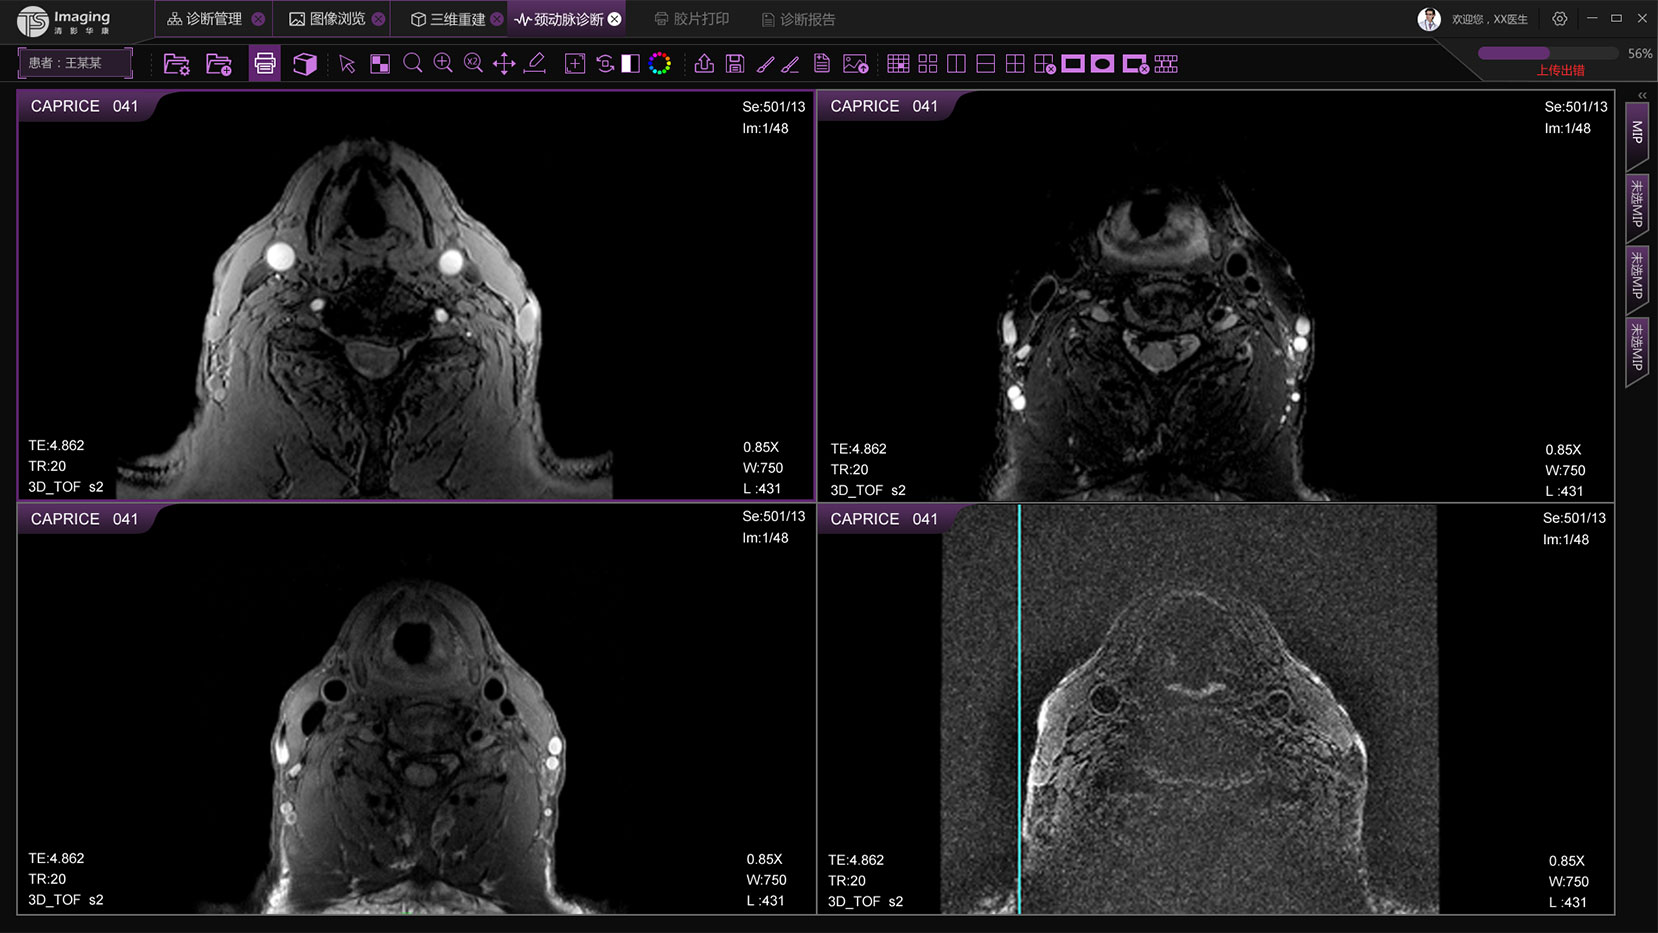

頸動脈診斷頁面

頸動脈診斷頁面整體布局和三維重建比較相似,最大的區(qū)別是右側(cè)的操作區(qū)域,血管分析都為按鍵操作,通過間隔的大小分成三部分。單層切片除了按鍵還有下拉菜單的操作。

頸動脈診斷原型